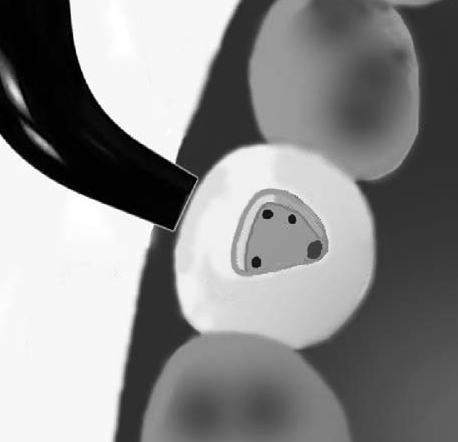

Como método

El conducto

y el orificio es

esencialmente

un agujero en

la raíz,

la

transmisión de luz

muestra

al orificio de entrada del conducto como una mancha

oscura en un fondo brillante. Ver imagen izquierda

superior,

la siguiente imagen es el resultado de utilizar una

cámara intraoral, con 10 aumentos (X10)

|

| En la

imagen derecha se observa el dispositivo de

transiluminación dentaria |